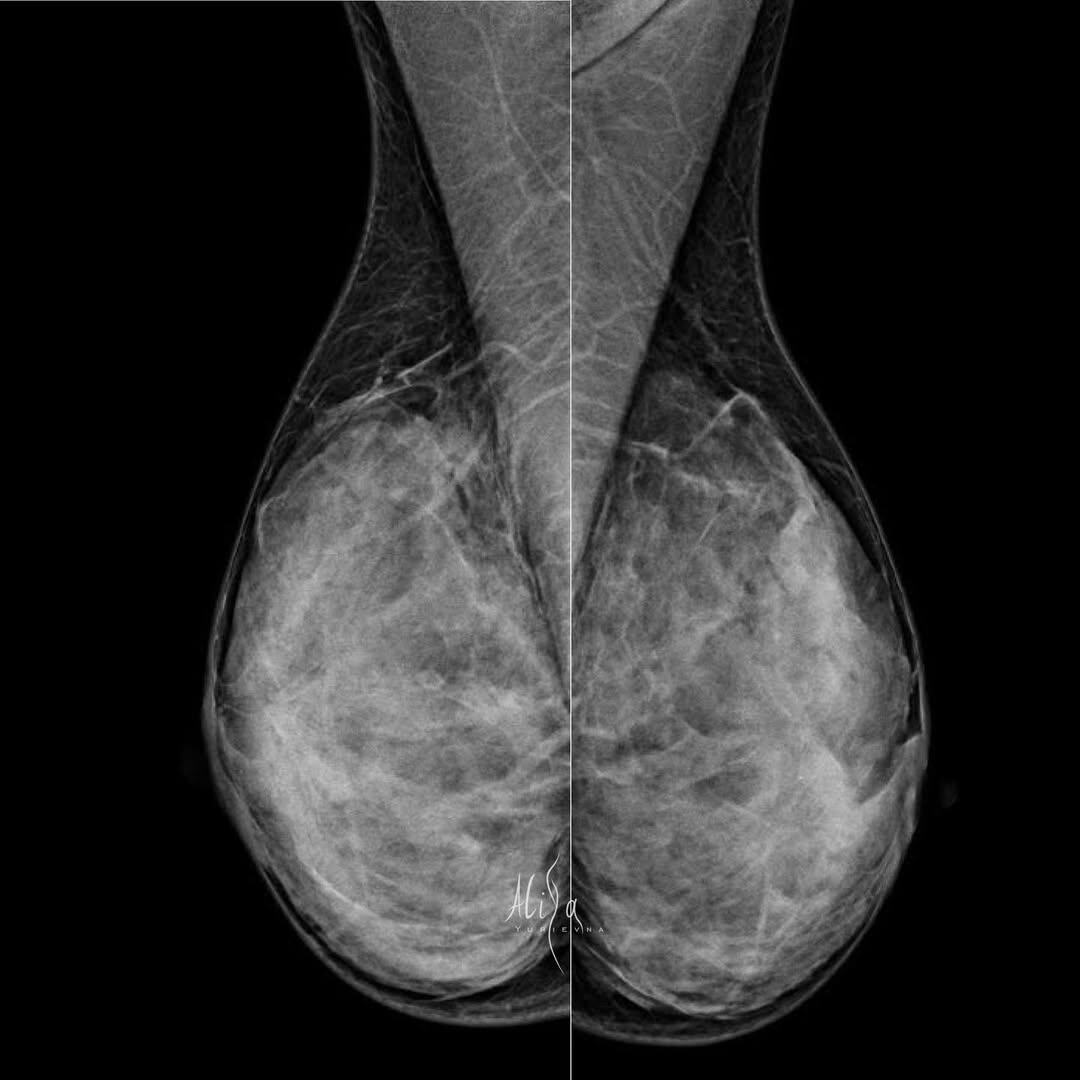

Кейс. Женщина 66 лет

Жалоб нет. Плотный рентгенологический фон. Всё как мы «любим». Выход единственный - освоить вторую модальность. УЗИ Молочных желёз. И плотная вуаль больше не будет преградой. ⠀ Инвазивная карцинома G1 молочной железы. Экспрессия рецепторов эстрогенов – 8 баллов, прогестеронов – 8 баллов, c-erbB2/HER2/neu – 1+. Маркер пролиферативной активности Ki67 имеют ~ 10% клеток. ⠀ #кейс

Жалоб нет. Плотный рентгенологический фон. Всё как мы «любим».

Выход единственный - освоить вторую модальность. УЗИ Молочных желёз. И плотная вуаль больше не будет преградой.

Инвазивная карцинома G1 молочной железы.

Экспрессия рецепторов эстрогенов – 8 баллов, прогестеронов – 8 баллов, c-erbB2/HER2/neu – 1+. Маркер пролиферативной активности Ki67 имеют ~ 10% клеток.